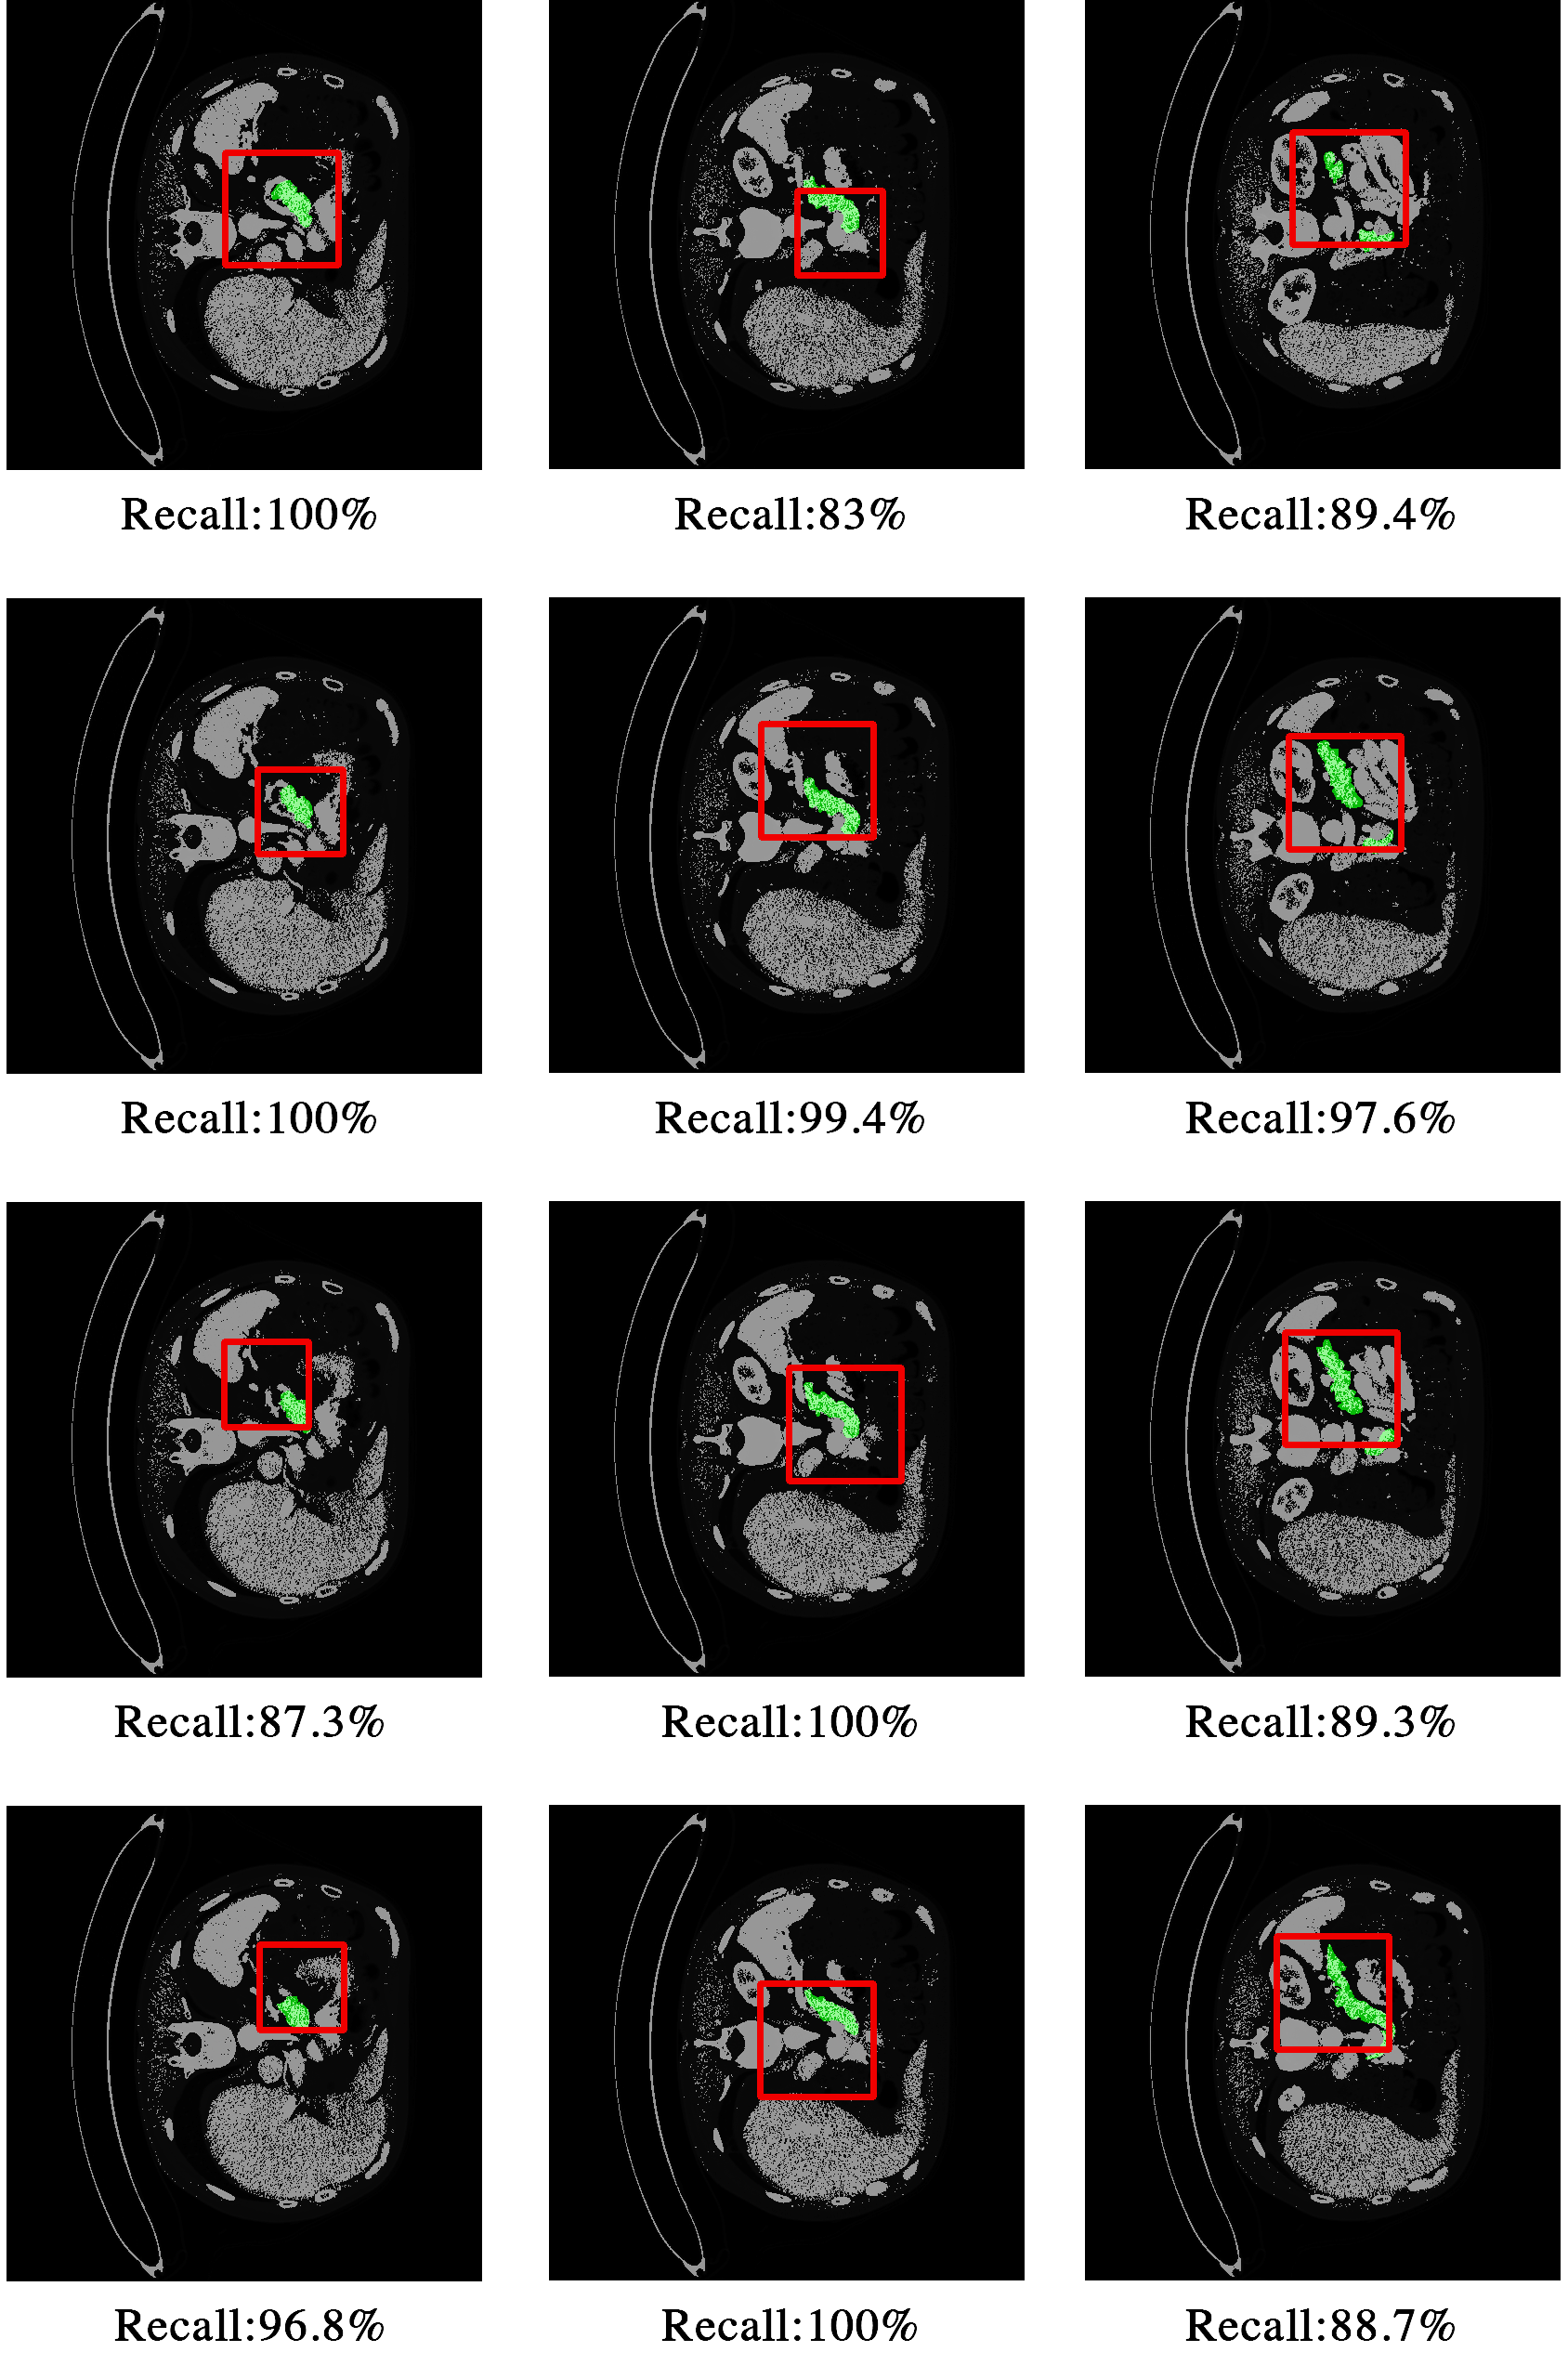

Refer to caption

Figure 9: Sample localization results of axial slices in volume 76. The pancreas is annotated in green, and the localization result is shown with a red bounding box. Small (pancreas fraction <0.1absent0.1<0.1, shown in first column), medium (pancreas fraction (0.1,0.15)absent0.10.15\in(0.1,0.15)), shown in second column) and large (pancreas fraction >0.15absent0.15>0.15, shown in third column) pancreas all achieve good localization results. Better viewed in color.

Localization for different sizes of pancreas. To illustrate the performance of our DQN-localization agent, we especially show the localization results of Volume 76’s axial slices in Fig.9. With Volume 76’s axial slices, we achieve an average recall rate of 89.7% and an average IoU of 0.11, which indicates that the main part of our target pancreas is retrieved. Note that axial scenario is the hardest one among three axes, however, sample results show stable bounding boxes despite the variance in pancreas size. The different sizes of triggered bounding boxes suggest that our agent may terminate without exhausting all the steps, and has learned the proper time to initiate a trigger action. Quantitative results of all testing samples are further discussed in Sec. 4.5.